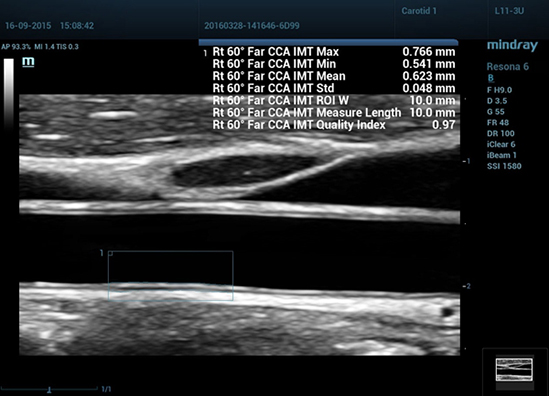

RIMT (RF-Data IMT — измерение толщины комплекса интима-медиа с помощью данных из радиодиапазона)

За счет содержащихся в необработанном акустическом сигнале данных из радиодиапазона (RF-Data), технология RIMT обеспечивает автоматическое измерение толщины КИМ в режиме реального времени с исключительно высокой точностью до 5 мкм, с количественным анализом в пределах 6 сердечных циклов и с меньшей зависимостью от качества изображения – все это значительно повышает точность диагностики.

• 09 Auto IMT

Авто IMT (толщина интимы-медии)